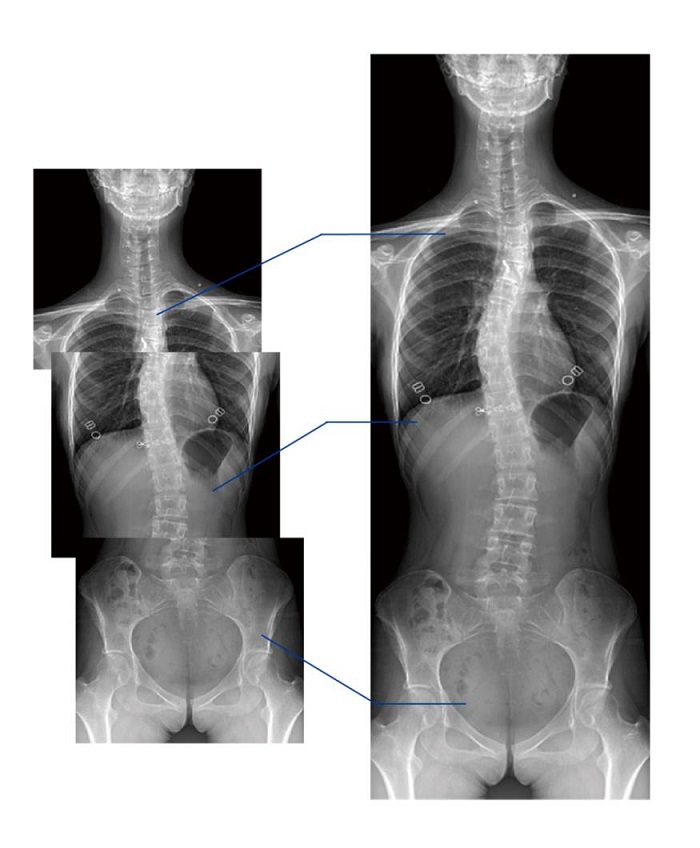

全景拼接功能

全景拼接功能是在全景影像拍攝的情況下,拍攝各個(gè)部位的影像,得到的圖像最終合成一幅全景圖像。適用于輔助脊柱畸形矯形治療、康復(fù)檢查,可對脊柱、下肢及下肢靜脈造影進(jìn)行分段攝片,然后對分段圖像進(jìn)行拼接,在一幅X光圖像上完整顯示全脊柱或下肢整體形態(tài),為臨床提供高精度圖像。